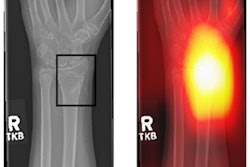

Chest x-ray and CT are considered the go-to modalities for diagnosing COVID-19, with many clinicians considering CT to be the better tool, the authors wrote. COVID-19 on CT exams tends to manifest in the lung as ground-glass opacities, peripheral distribution, multilobular involvement, and bilateral lesion involvement.

"Physicians can identify a more detailed disease picture by using a CT scan than by using conventional x-rays," they explained. "Moreover, a CT scan can identify the exact problem location more precisely."

For their study, Alshayeji and colleagues included 750 CT images taken from the China National Centre for Bioinformation to develop a machine-learning-based algorithm that could be incorporated into a CAD system and hopefully improve both diagnosis and treatment of the illness. The image dataset included both infected and healthy individuals; the machine-learning results were used to flag any pertinent features indicating either condition. The team categorized CT disease severity scores as mild (lesion covers less than 25% of lung area); moderate (25% to 50% of lung area); and severe (greater than 50%).